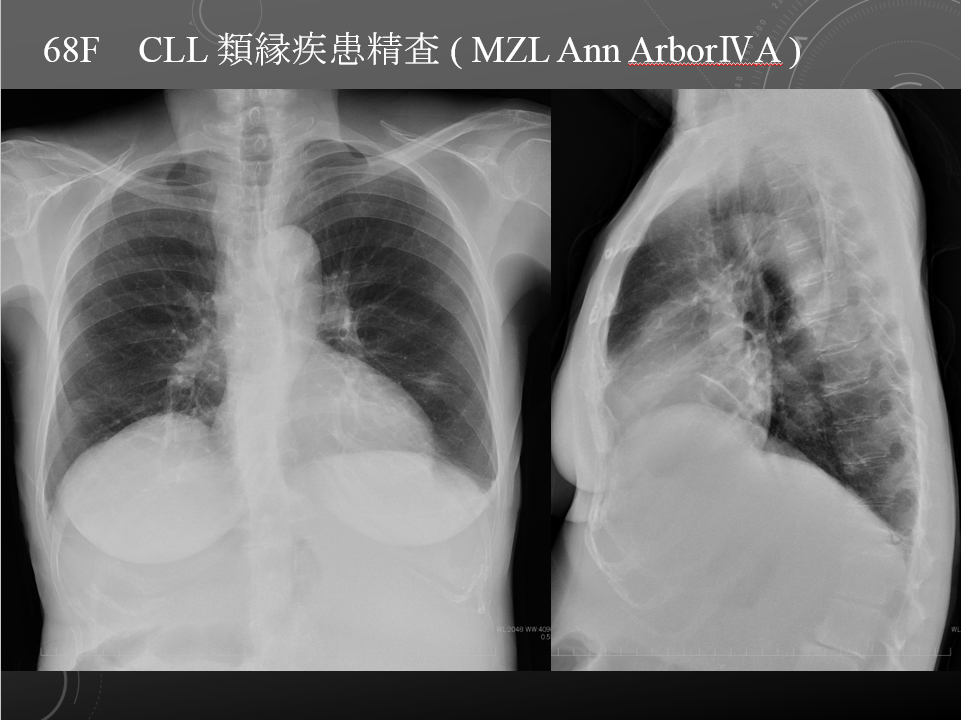

68F 著明な脾腫 CLL類縁疾患 MZL Ann ArborⅣAらしい